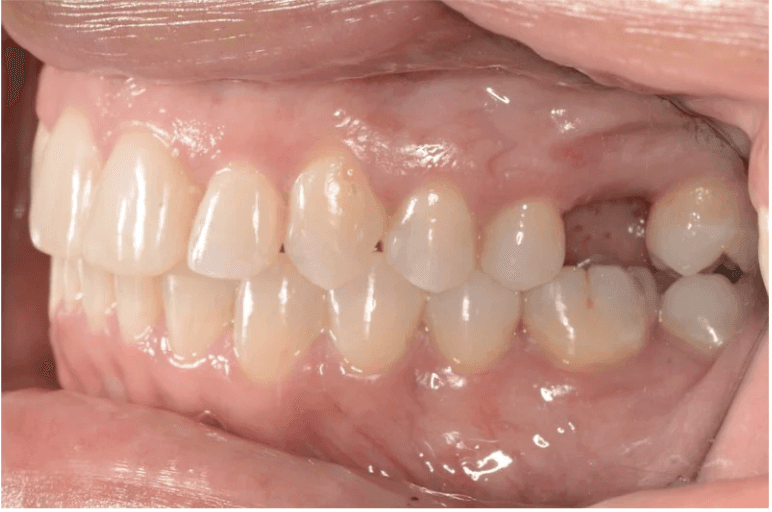

Initial treatment

INTRAORAL

Final results